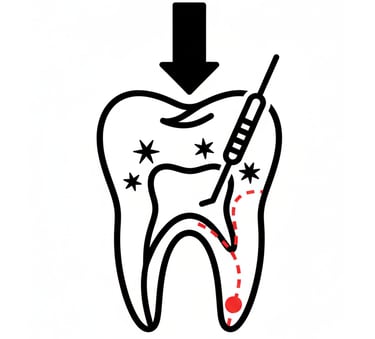

Ενδοδοντική θεραπεία (Απονεύρωση)

Η ενδοδοντική θεραπεία επεμβαίνει στο εσωτερικό του δοντιού (τον πολφό), όπου βρίσκονται νεύρα και αγγεία. Σκοπός της είναι να αφαιρεθεί ο μολυσμένος ή φλεγμονώδης ιστός, να καθαριστούν και να σφραγιστούν οι ριζικοί σωλήνες, ώστε να σωθεί το δόντι και να εξαλειφθεί ο πόνος ή η λοίμωξη.